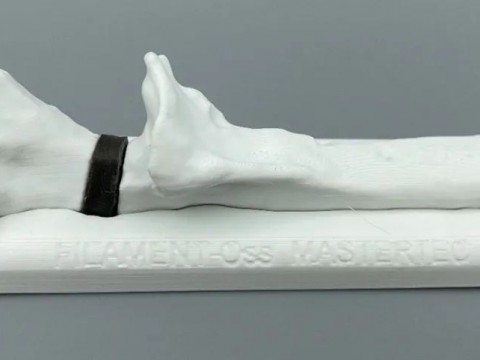

- 邯郸市第一医院3D打印技术指导马蹄内翻高弓足截骨矫形四关节融合术

0评论2022-02-14